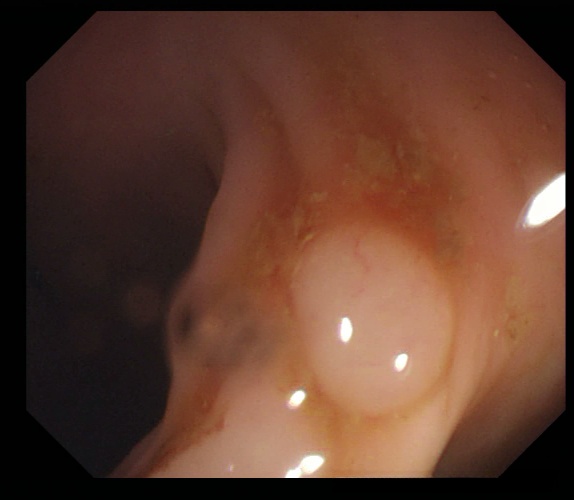

4、Kvasir : 该医学影像数据集是由挪威癌症登记处与挪威放射学协会共同发起开发的。该数据集包含了大量CT扫描图像资料,并旨在促进对肺结节及结肠息肉的自动检测与分割研究。

处理好后的COCO格式的数据集图像的总数为1000张,类型标签为病灶区域。